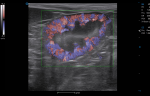

Abdominal Applications

● Micro Flow captures micro blood flow signals to precisely reflect the blood flow perfusion status in organs.